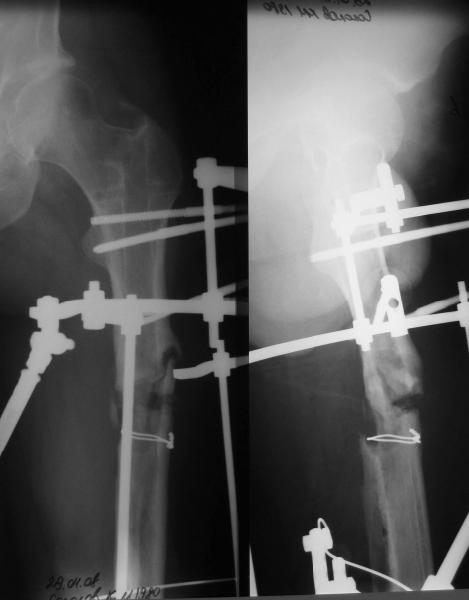

Пациент попал под наше наблюдение через 3 недели после первого остеосинтеза (фото 1). Учитывая, нестабильность остеосинтеза, выстоящий стержень закрыто перештифтовали (фото 2), через 3 месяца динамизация. К 5 месяцам имели укорочение 2 см, при том, что динамический винт стал статическим. От дальнейшей динамизации отказались, учитывая наличие контакта между фрагментами и возможность прогрессирования укорочения. К 1,5 года сращение не достигнуто (фото 3). Удалили гвоздь, выполнили дистракционный остеосинтез с целью стимуляции остеогенеза и компенсации укорочения (фото 4), потом закрыто перештифтовали после рассверливания (фото 5). На сегодняшний день, через 4 месяца после последней операции (фото 6) признаков регенерата нет, длина восстановлена, ходит без дополнительной опоры.